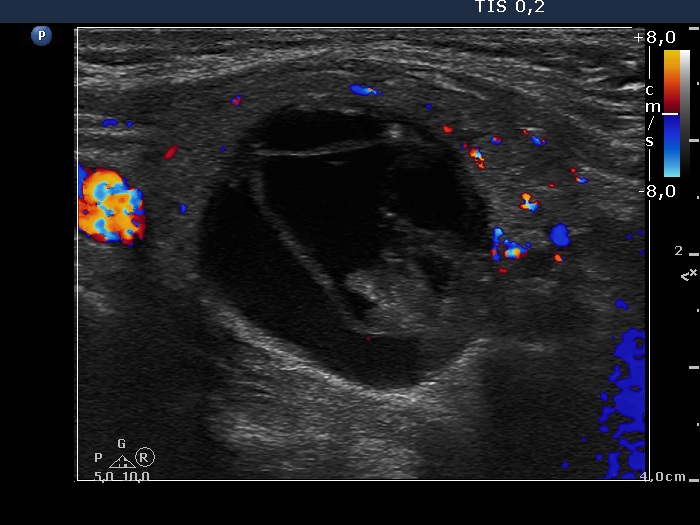

Left lobe, longitudinal scan, color Doppler mode. The vascularization is not specific.